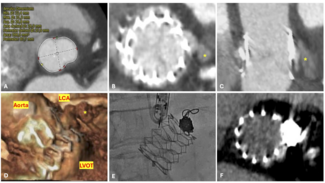

A 59-year-old man was referred to our institution for potential MitraClip (Abbott Vascular) therapy after he was found to have severe mitral regurgitation (MR) seen on transthoracic echocardiography. He had a history of coronary artery disease and functional MR, and underwent coronary artery bypass grafting and mitral annuloplasty (28 mm CG Future; Medtronic Inc.) 4 years prior at an outside institution. A permanent pacemaker was also implanted for advanced atrioventricular block. The procedure was complicated by a methicillin-resistant  staph aureus sternal wound infection requiring multiple debridements and wound vacuum drainage for 1 year. There was no documented bacteremia at that time. Three years later, he had several admissions for decompensated heart failure, volume overload, and pulmonary edema without angina pectoris. Transthoracic echocardiogram revealed left ventricular (LV) ejection fraction of 55%, severe MR with 2 distinct regurgitant jets, and an estimated right ventricular pulmonary systolic pressure of 60 mm Hg. Subsequent transesophageal echocardiography (TEE) demonstrated a dilated mitral annulus with the septal-lateral dimension measuring 36 mm. There was significant dehiscence of the annuloplasty ring from the posterior annulus and focal dehiscence at the right fibrous trigone, with a resultant 6 x 8 mm perforation at the base of the anterior mitral leaflet (Figure 1). There was 4+ MR through the mitral leaflet perforation and 1+ central MR. There was trivial regurgitation through the posterior dehiscence (Figure 2). After referral to our center, 3.5 years after the original operation, several blood cultures drawn on different days were negative and an erythrocyte sedimentation rate was normal. Angiography demonstrated occluded vein grafts to the left circumflex and right coronary arteries with severe native diffuse disease not amenable to percutaneous or surgical revascularization. The left internal mammary artery graft to left anterior descending artery was patent. In view of his related comorbidities and prior sternal wound infection, percutaneous repair of the anterior mitral leaflet perforation was performed.

staph aureus sternal wound infection requiring multiple debridements and wound vacuum drainage for 1 year. There was no documented bacteremia at that time. Three years later, he had several admissions for decompensated heart failure, volume overload, and pulmonary edema without angina pectoris. Transthoracic echocardiogram revealed left ventricular (LV) ejection fraction of 55%, severe MR with 2 distinct regurgitant jets, and an estimated right ventricular pulmonary systolic pressure of 60 mm Hg. Subsequent transesophageal echocardiography (TEE) demonstrated a dilated mitral annulus with the septal-lateral dimension measuring 36 mm. There was significant dehiscence of the annuloplasty ring from the posterior annulus and focal dehiscence at the right fibrous trigone, with a resultant 6 x 8 mm perforation at the base of the anterior mitral leaflet (Figure 1). There was 4+ MR through the mitral leaflet perforation and 1+ central MR. There was trivial regurgitation through the posterior dehiscence (Figure 2). After referral to our center, 3.5 years after the original operation, several blood cultures drawn on different days were negative and an erythrocyte sedimentation rate was normal. Angiography demonstrated occluded vein grafts to the left circumflex and right coronary arteries with severe native diffuse disease not amenable to percutaneous or surgical revascularization. The left internal mammary artery graft to left anterior descending artery was patent. In view of his related comorbidities and prior sternal wound infection, percutaneous repair of the anterior mitral leaflet perforation was performed.

The procedure was performed under general anesthesia with three-dimensional TEE guidance, and periprocedural prophylactic antibiotics were given. The anterior mitral leaflet perforation measured 6 x 8 mm (area, 0.37 cm2), and the anterior mitral leaflet length was measured at 22 mm. As the left atrial (left ventricular, for this case) disc for a 5 mm Amplatzer septal occluder (St. Jude Medical) was 17 mm, it was felt that the device would not restrict the motion of the leaflet and still adequately seal the perforation.

The procedure was performed under general anesthesia with three-dimensional TEE guidance, and periprocedural prophylactic antibiotics were given. The anterior mitral leaflet perforation measured 6 x 8 mm (area, 0.37 cm2), and the anterior mitral leaflet length was measured at 22 mm. As the left atrial (left ventricular, for this case) disc for a 5 mm Amplatzer septal occluder (St. Jude Medical) was 17 mm, it was felt that the device would not restrict the motion of the leaflet and still adequately seal the perforation.

Initially, right heart catheterization was performed that demonstrated pulmonary arterial pressure of 40/20 with mean pulmonary capillary wedge pressure of 18 mm Hg and V waves up to 22 mm Hg. Simultaneously, left heart catheterization revealed LV end diastolic pressure of 17 mm Hg, ruling out mitral stenosis. A BRK needle (St. Jude Medical) was used to perform transseptal puncture under echocardiographic guidance and a Mullins transseptal sheath (Medtronic Inc.) was advanced through the interatrial septum in a superior location within the fossa ovalis. Intravenous heparin was given at this point. Mean left atrial pressure was recorded at 18 mm Hg with prominent V waves up to 40 mm Hg. The Mullins sheath was then removed and a medium curl Agilis NxT catheter (11.5 Fr outer diameter, 8.5 Fr inner diameter, St. Jude Medical) was advanced into the left atrium and directed toward the base of the anterior mitral leaflet. Through the Agilis catheter, an 8 Fr EBU 3.75 guiding catheter (Medtronic Inc.) was then advanced to its tip. Another multipurpose catheter was then nested through the guiding catheter using a triple telescoping “mother and child” approach. An exchange-length 0.035˝ angled Glidewire (Terumo Medical Corporation) was then advanced through the leaflet perforation using three-dimensional TEE guidance in an antegrade fashion. Over the Glidewire, the multipurpose catheter was passed through the defect into the LV apex. The Glidewire was then exchanged for an Amplatz Superstiff wire (Boston Scientific), over which the EBU guiding catheter was advanced in the LV cavity (Figure 2). Once the guiding catheter was appropriately positioned in the LV midcavity, the multipurpose catheter as well as the stiff wire were removed. Then, a 5 mm Amplatzer atrial septal occluder was loaded into the guiding catheter and deployed successfully to the anterior mitral leaflet perforation under TEE guidance (Figure 3). On color Doppler, there was no residual MR through the leaflet perforation and only 1+ functional (central) MR with excellent device stability (Figures 1 and 4). The anterior mitral leaflet had preserved mobility and there was no obstruction of the LVOT (Figure 4). Mean left atrial pressure after the repair was 15 mm Hg with diminished V waves. Final transmitral gradient was 4 mm Hg with mitral valve area of 2.5 cm2. Procedural fluoroscopy time was 27 minutes. The postprocedure course was uneventful and the patient was discharged on aspirin and clopidogrel on postprocedure day 1. At 1-month follow-up, he was in New York Heart Association functional class I. He developed transient mild hemolytic anemia, which did not require transfusion. On follow-up echocardiogram, there was no residual MR through the defect and only 1+ central MR.

Initially, right heart catheterization was performed that demonstrated pulmonary arterial pressure of 40/20 with mean pulmonary capillary wedge pressure of 18 mm Hg and V waves up to 22 mm Hg. Simultaneously, left heart catheterization revealed LV end diastolic pressure of 17 mm Hg, ruling out mitral stenosis. A BRK needle (St. Jude Medical) was used to perform transseptal puncture under echocardiographic guidance and a Mullins transseptal sheath (Medtronic Inc.) was advanced through the interatrial septum in a superior location within the fossa ovalis. Intravenous heparin was given at this point. Mean left atrial pressure was recorded at 18 mm Hg with prominent V waves up to 40 mm Hg. The Mullins sheath was then removed and a medium curl Agilis NxT catheter (11.5 Fr outer diameter, 8.5 Fr inner diameter, St. Jude Medical) was advanced into the left atrium and directed toward the base of the anterior mitral leaflet. Through the Agilis catheter, an 8 Fr EBU 3.75 guiding catheter (Medtronic Inc.) was then advanced to its tip. Another multipurpose catheter was then nested through the guiding catheter using a triple telescoping “mother and child” approach. An exchange-length 0.035˝ angled Glidewire (Terumo Medical Corporation) was then advanced through the leaflet perforation using three-dimensional TEE guidance in an antegrade fashion. Over the Glidewire, the multipurpose catheter was passed through the defect into the LV apex. The Glidewire was then exchanged for an Amplatz Superstiff wire (Boston Scientific), over which the EBU guiding catheter was advanced in the LV cavity (Figure 2). Once the guiding catheter was appropriately positioned in the LV midcavity, the multipurpose catheter as well as the stiff wire were removed. Then, a 5 mm Amplatzer atrial septal occluder was loaded into the guiding catheter and deployed successfully to the anterior mitral leaflet perforation under TEE guidance (Figure 3). On color Doppler, there was no residual MR through the leaflet perforation and only 1+ functional (central) MR with excellent device stability (Figures 1 and 4). The anterior mitral leaflet had preserved mobility and there was no obstruction of the LVOT (Figure 4). Mean left atrial pressure after the repair was 15 mm Hg with diminished V waves. Final transmitral gradient was 4 mm Hg with mitral valve area of 2.5 cm2. Procedural fluoroscopy time was 27 minutes. The postprocedure course was uneventful and the patient was discharged on aspirin and clopidogrel on postprocedure day 1. At 1-month follow-up, he was in New York Heart Association functional class I. He developed transient mild hemolytic anemia, which did not require transfusion. On follow-up echocardiogram, there was no residual MR through the defect and only 1+ central MR.

For percutaneous leaflet repair, high-quality two-and three-dimensional TEE are essential to delineate defect dimensions and motion of the anterior mitral leaflet in relation to the left ventricular outflow tract (LVOT). We utilized real-time three-dimensional TEE of the mitral valve as well as fluoroscopy to direct the guiding catheter and deploy the device. A triple-telescoping catheter technique that has been previously described was used to cross the very medial and somewhat posterior defect.20 For device selection, it is important to consider the diameters of the waist and two retention discs. We chose an Amplatzer septal occluder due to the very low profile and small disc diameters, which minimized the potential of restricting leaflet motion or obstructing the LVOT. Although use of an Amplatzer vascular plug has been described for a mitral leaflet perforation as a complication of mechanical aortic valve replacement, this device has substantial height and may not be the ideal choice for patching a leaflet perforation.7